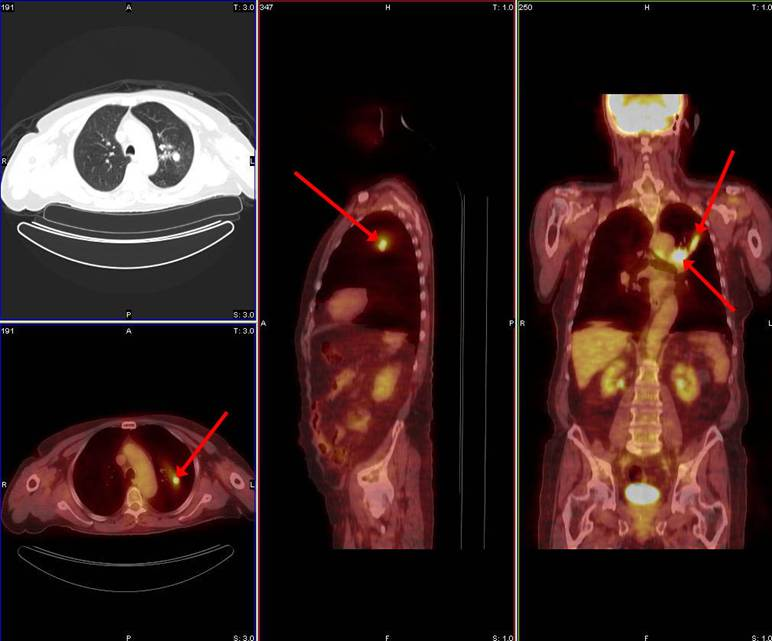

Breakdown what PET/CT is a combination of (what each part specifically scans)

PET – scans the patient’s physiology

CT – scans the patient’s anatomy

What type of process is commonly seen in cancer?

Metabolic process – hypermetabolic

Why do we like to use FDG as a pharmaceutical in PET?

It’s a sugar that is very similar to glucose

As cancer uses metabolic processes, it uses glucose as its main form of energy – we take advantage of this by binding the radioactive material with a pharmaceutical that’s similar in structure to glucose so that we can visualize where the cancer is based on its metabolism

What happens to the FDG when it’s up-taken by the cancer cells?

Instead of breaking down FDG and using it as energy, it will just accumulate in the cancer cell – makes the cancer more visible on our PET images

Are there other organs in our body that will uptake the tracer F-18 FDG?

Brain

Kidneys

Bladder

Variable of the heart